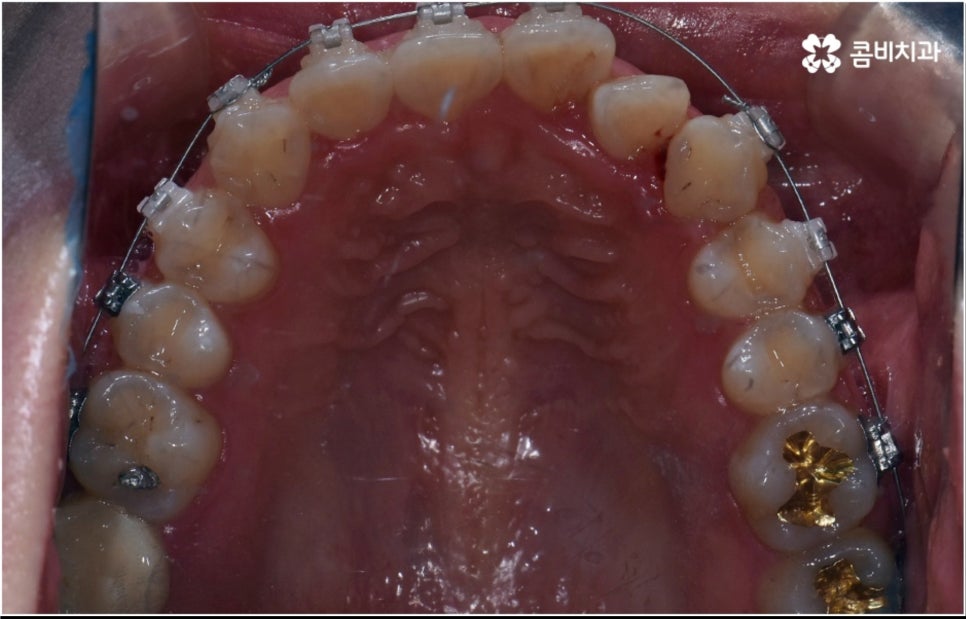

3D CT 등 정밀 검진 기계를 통해 꼼꼼하게 검진을 한 후 환자분들의 부정교합의 종류 및 정도 등에 따라 각자에게 맞는 교정 치료 계획을 수립하게 되는데, 내부 공간이 얼마나 있는지에 따라 발치가 필요한지 아닌지 여부도 달라지고 또 같은 부정교합이라고 해도 사람마다 잇몸 건강이나 치근 상태 등에 따라 잇몸뼈가 벌어지면서 치아가 이동하는 속도, 치아가 자리잡는 양상 등도 모두 달라지기 때문에 성인 치아교정 기간 총 소요 시간은 모두 달라질 수 밖에 없을 거예요.

물론 일반적으로 성장기보다는 잇몸뼈가 굳어진 이후 성인 치아교정 기간 이 길어질 수 밖에 없으나 이 역시 케이스별로 달라질 수 있어요. 예를 들어 만약 임플란트를 심으려고 할 때 공간이 없거나 주변 치열이 삐뚤어져서 어려움이 있기 때문에 하는 교정이거나 앞니 일부가 조금 벌어지고 살짝 각도가 앞으로 나와 있는 등 별다른 골격적 문제 없이 기능성 및 심미성을 보다 개선해 주기 위해서 하는 교정의 경우는 부분 교정으로 진행하기 때문에 보통 발치 과정도 포함되지 않고 성인 치아교정 기간 도 6~8개월 정도로 보다 빠르게 끝날 수 있습니다.

하지만 부정교합의 정도가 심하거나 골격적 문제를 바로잡아 주어야 하는 경우는 전체 교정을 진행해야 하기 때문에 (환자분들마다 다르지만) 평균적으로 18~36개월 정도의 성인 치아교정 기간 이 소요되며, 중장년 성인분들 중에 잇몸 질환 등으로 구강 건강이 약해져 있는 분들의 경우에는 더욱 환자분들의 상황에 맞게 필요한 치료를 병행하면서 무리하지 않은 진행을 해야 하기 때문에 전체 기간이 좀 더 늘어날 수 있어요.

치아 색상의 세라믹 브라켓을 이용하는 장치들은 예전 메탈 장치 보다 심미성이 훨씬 보완되었으며, 치아 뒤쪽에 장치를 부착하여 아예 눈에 띄지 않는 설측교정장치나 언뜻 보면 티가 잘 나지 않는 얇고 투명한 특수 강화 플라스틱을 이용하는 투명교정장치를 이용하면 교정을 하고 있다고 본인이 말을 하지 않으면 잘 모를 정도로 심미성이 뛰어나기 때문에 각 장치들의 소재와 특성, 장단점에 대해서 잘 알아보고 신중한 선택을 하는 것이 중요하다고 할 수 있어요.